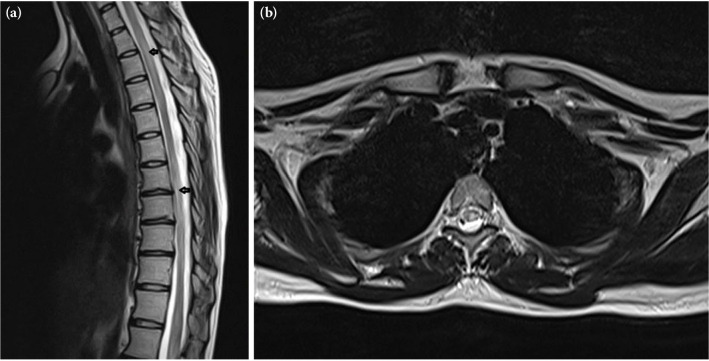

横贯脊髓炎是一种罕见的疾病,以脊髓炎症为特征。这些表现可能与原发性运动神经元损伤有关,也可能与非特异性表现有关,如四肢肌肉力量和感觉丧失。在此,我们报告了一名21岁的女性横脊髓炎患者,主诉为肌肉无力和尿失禁,经腰椎成像诊断为腰椎间盘突出,手术后症状没有改善。

Transverse myelitis is a rare disease characterized by inflammation of the spinal cord. These findings may present with findings related to primary motor neuron damage or with nonspecific findings, such as loss of muscle strength and sensation in the extremities. Herein, we presented a 21-year-old female patient with transverse myelitis with complaints of muscle weakness and urinary incontinence who was diagnosed with lumbar disc herniation after lumbar imaging and whose complaints did not improve after surgery.